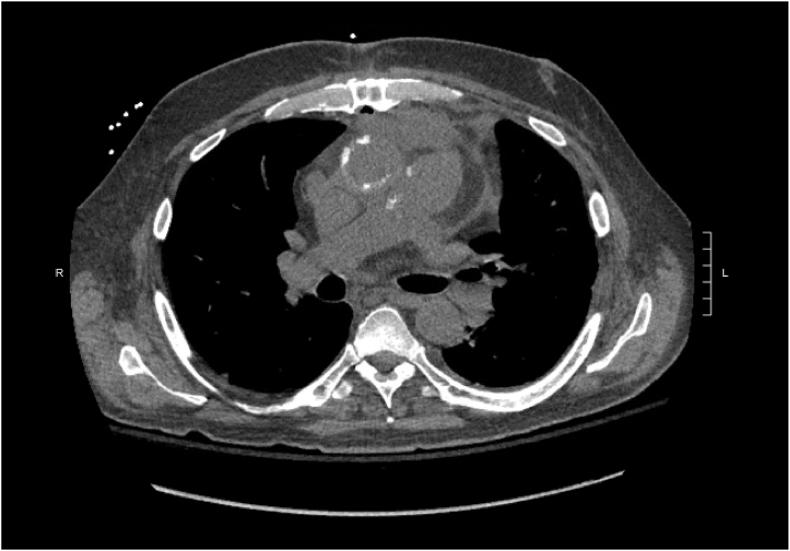

Donor-derived invasive fungal infections among solid organ transplant recipients are rare but sometimes devastating events associated with notable morbidity and mortality. Here we describe two donor-derived fungal infections - one complex infection and one infection - that occurred among heart transplant recipients at a quaternary care center. Both recipients survived their infections, though with substantial morbidity despite aggressive surgical intervention and antifungal therapy.

实体器官移植受者中供体来源的侵袭性真菌感染很少见,但有时是具有显著发病率和死亡率的灾难性事件。在此,我们描述了在一家四级医疗中心心脏移植受者中发生的两例供体来源的真菌感染——一例复杂感染和一例单一感染。两名受者均从感染中存活下来,尽管经过积极的手术干预和抗真菌治疗,仍有严重的发病率。